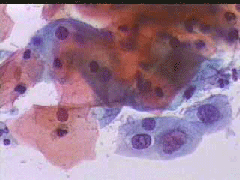

Α΄φορα σε μας 6.10. 2004 για προληπτικο έλεγχο.. Στο ιστορικο: Το 2001 λαπαροτομια και αφαιρεση δερμοειδών κύστεων άμφω... Προσήλθε λογω νέας διάγνωσης μικρης κύστεως ωοθήκης που δεν επιβεβαιωθηκε. Συνέστησα να την δω μετα την περιοδο, επειδή στην εξεταση εμφάνιζε μια ελαφρα ευαισθησια στον αρ. θόλο του κόλπου, εκει που ψηλαφάται καμια φορά ο κάτω πόλος της ωοθήκης.. Προσηλθε την 15.12.2009 για έλεγχο... Τωρα υφίσταται κολποσκοπικό ευρημα στον τράχηλο... Αρνητική περιοχή στις δοκιμασίες οξικου οξεως και Lugol, χωρίς εικόνα μωσαϊκού, όπως σε επουλωτικές διαδικασίες... Τότε μου ειπε ότι ενδιαμεσως προηγηθηκε αλλού καυτηριασμός... Το Papanicolaou-test, από το οποιο προερχονται οι ακόλουθες εκόνες, συνηγορούσε για δυσπλασία τουλαχιστον CIN II.. Δεν θέλησε να γινει βιοψία αμέσως... Ηλθε παλι τον Μαρτιο 2005... Στην μικροβιοψία προέκυψε CIN III..

Papanicolaou test 15.12.2004

Πλακωδη επιθηλιακά κύτταρα κυρίως της επιφανειακής και λιγώτεροτης διαμέσουστιβάδας. . Λίγα της παραβασικής καθώ και πολύλίγα του ενδοτραχήλου .. Σε πολλάοπτικάπεδία ομάδες κυττάρων της παραβασικής και λιγων της διαμεσου στιβαδος, με διογκωμένους, αρραιοχρωματικούς και ανισομεγέθειςπυρήνες, με καλή δομήχρωματίνης. Kαθαρό υπόστρωμα. Yπόνοια για δυσπλασία σοβαρού βαθμού (CIN II-III)